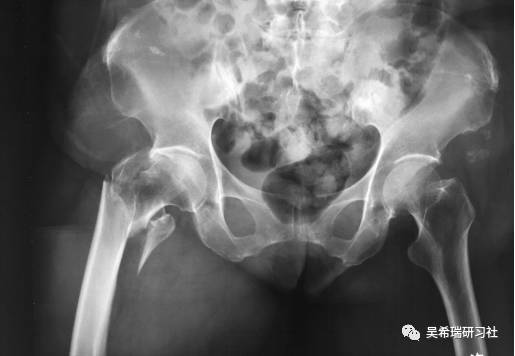

病例8

双下肢车祸外伤保肢的理由是足底皮肤好

TIPS:清创&盐水冲洗(不用双氧水)VSD骨水泥技术&开放植骨单边外固定架(下胫腓联合固定)早期下地 生理应力 + 机械应力游离植皮 / 不用皮瓣清创时游离皮质骨去除胫跖骨牵引技术防治&纠正足下垂